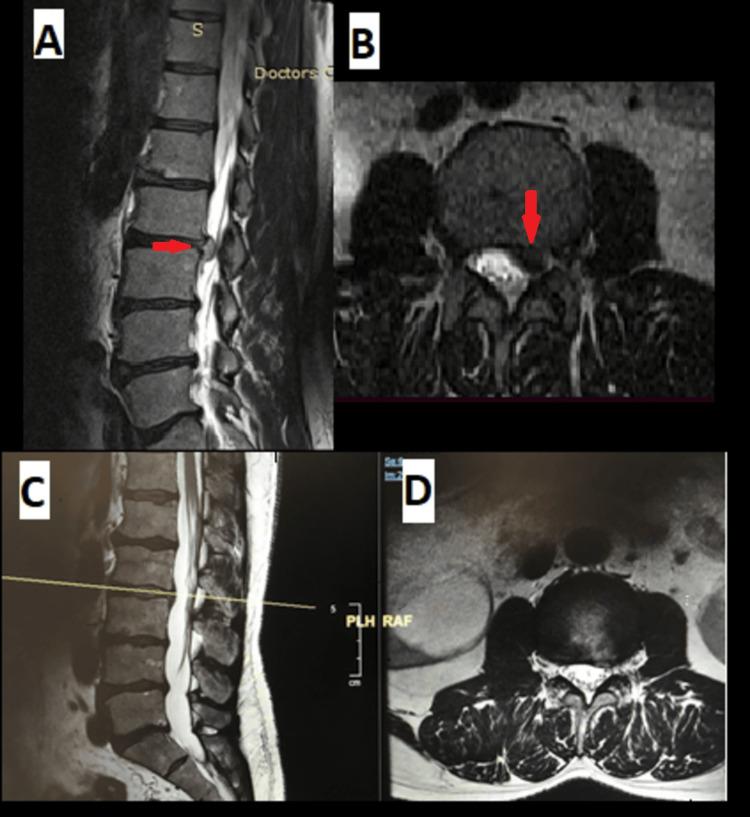

The main objective was to describe the different types and characteristics of lumbar spine extradural cysts and their optimal treatment options with a focus on endoscopic technique. We searched Pubmed, EMBASE, Medline, and Google Scholar for articles published between 1967 and 2020 using the keywords "Spinal Cyst," "Extradural Cyst," and "Lumbar Cyst." The various anatomical and histological types of the extradural cysts with their presentations, etiologies, imaging, and optimal treatment with a focus on endoscopic techniques were reviewed from the articles. Lumbar spinal cysts are relatively rare pathologies that might cause radicular symptoms similar to lumbar disc herniation. Spinal extradural cysts are classified either histologically based on the cyst lining tissues (synovial cysts or non-synovial, ganglion cysts) or anatomically based on the structure of origin (epidural cysts, ligamentum flavum cysts, discal cysts, post-discectomy pseudocysts, posterior longitudinal ligament cysts, facet cysts). Surgical excision is the recommended treatment of symptomatic cysts with endoscopic techniques being a viable option. Extradural lumbar cysts can be identified based on their histological structure or depending on their structure of origin. Regardless of their classification, they could all give similar clinical findings, and the optimal treatment would be surgical excision with endoscopic technique being a viable option with a satisfactory outcome.

主要目的是描述腰椎硬膜外囊肿的不同类型和特征及其最佳治疗方案,重点是内镜技术。我们在PubMed、EMBASE、Medline和谷歌学术搜索了1967年至2020年发表的文章,使用关键词“脊髓囊肿”“硬膜外囊肿”和“腰椎囊肿”。从这些文章中回顾了硬膜外囊肿的各种解剖学和组织学类型,及其表现、病因、影像学和以内镜技术为重点的最佳治疗方法。腰椎脊髓囊肿是相对罕见的病变,可能导致与腰椎间盘突出症相似的神经根症状。脊髓硬膜外囊肿根据囊肿内衬组织在组织学上分类(滑膜囊肿或非滑膜囊肿、神经节囊肿),或根据起源结构在解剖学上分类(硬膜外囊肿、黄韧带囊肿、椎间盘囊肿、椎间盘切除术后假性囊肿、后纵韧带囊肿、关节突囊肿)。手术切除是有症状囊肿的推荐治疗方法,内镜技术是一种可行的选择。硬膜外腰椎囊肿可以根据其组织结构或起源结构来识别。无论其分类如何,它们都可能给出相似的临床发现,最佳治疗方法是手术切除,内镜技术是一种可行的选择,效果令人满意。